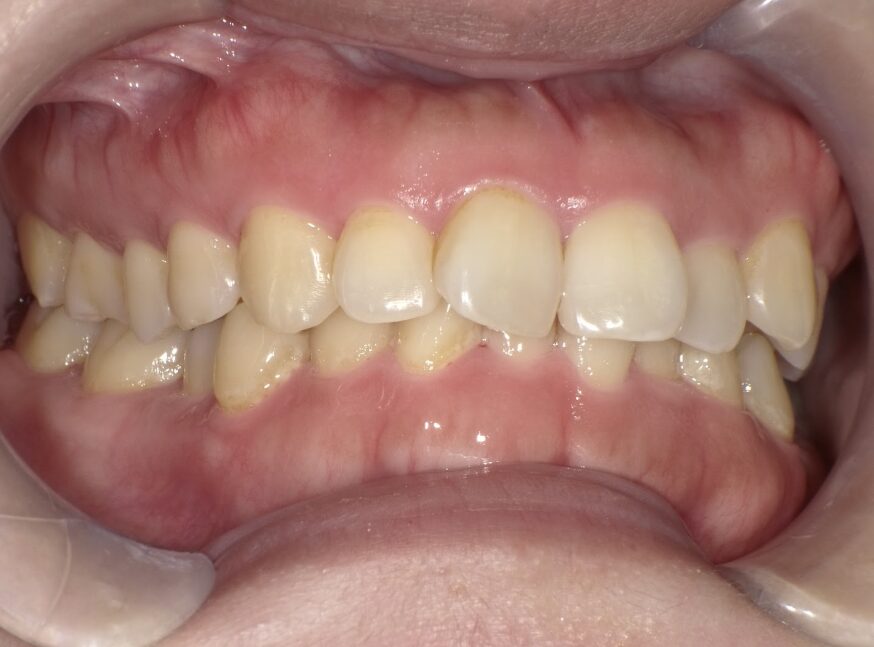

過蓋咬合

ガタガタを主訴に当院を受診され、上下前歯部に叢生(ガタガタ)と過蓋咬合(上の歯が下の歯を深く覆いかぶさっている状態)を認めました。

IPRを使用してマウスピース型矯正装置(インビザライン)を使用し過蓋咬合及び叢生の改善を行いました。

年齢/性別30代女性

抜歯部位非抜歯

治療期間1年6ヶ月